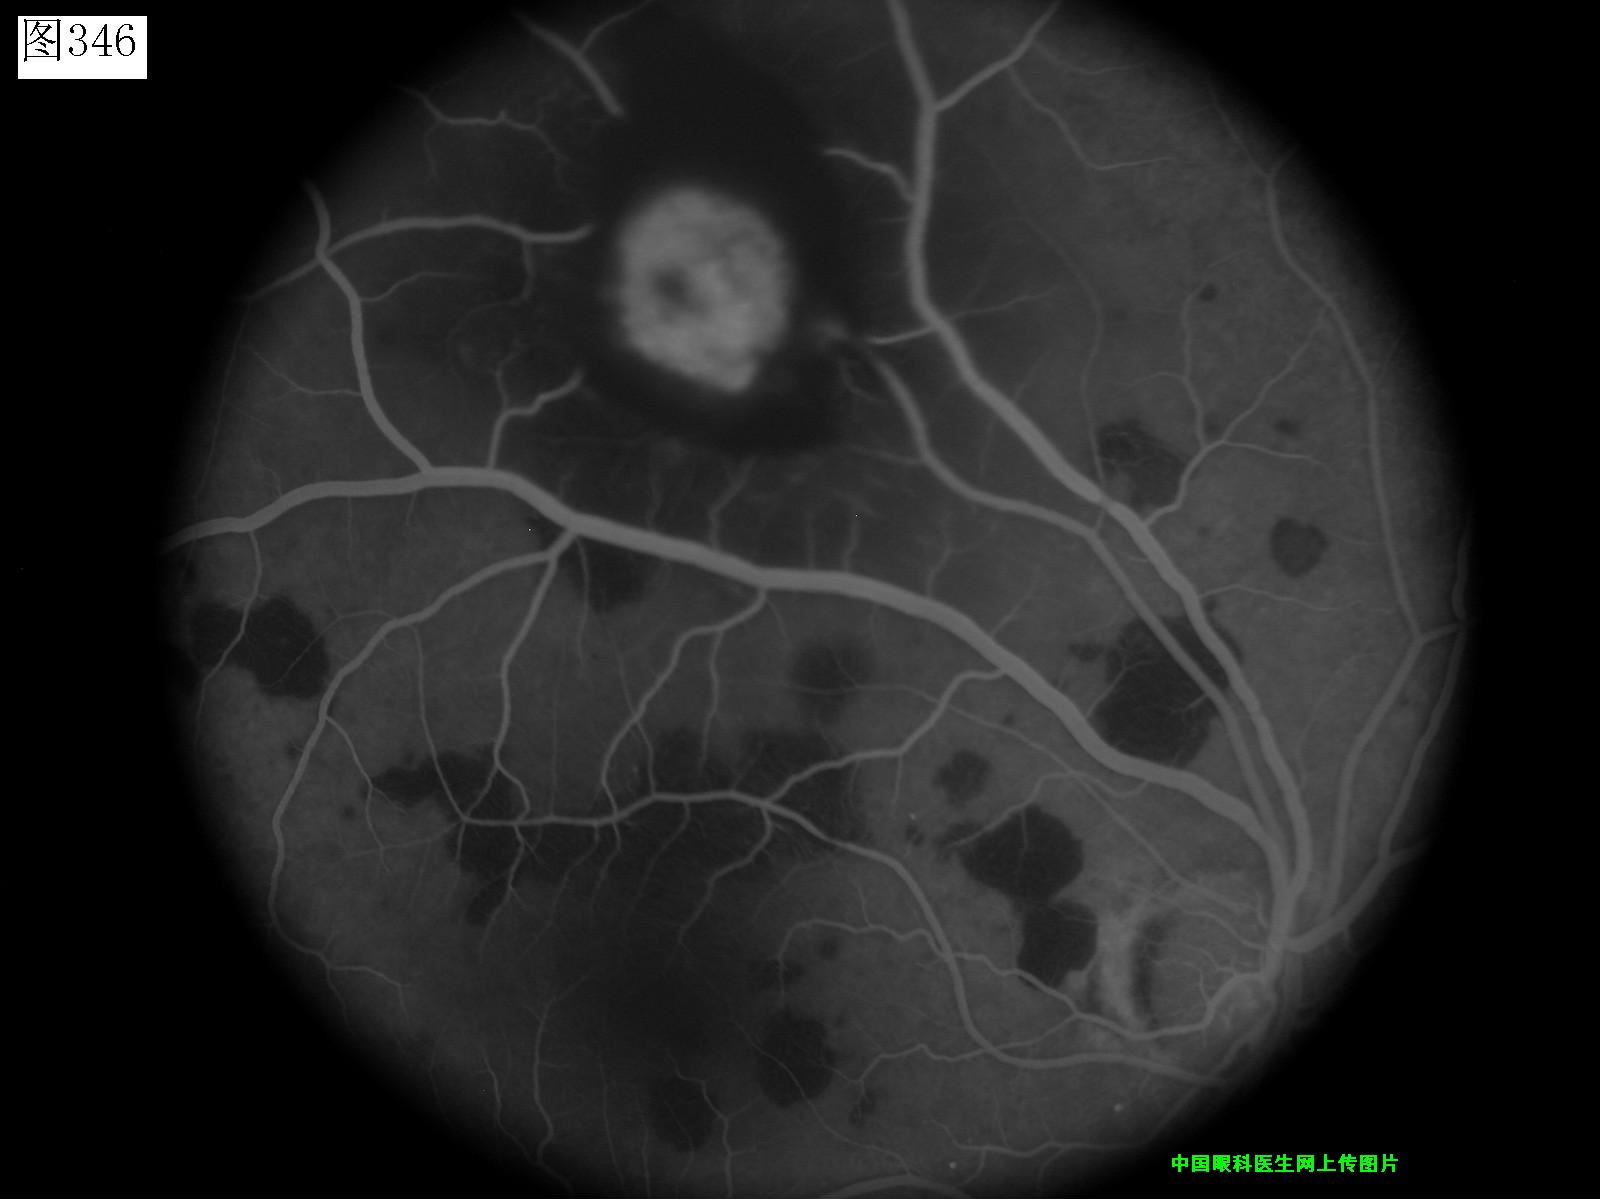

345 346 347 348